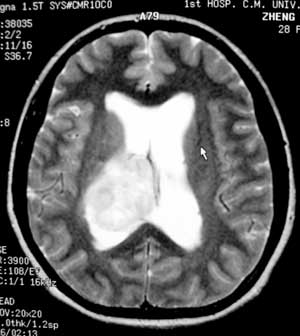

女性,28岁。头痛请会诊

右侧丘脑类圆形等t1,长t2病灶,t1增强明显强化。

女性,28岁。头痛请会诊。

考虑:①丘脑胶质瘤可能大。②脑积水。

t1等信号内出现点状高信号,考虑为出血灶,肿块内侧可见弧形低信号,为脑积液影。长t2,其内有混杂信号,周壁强化明显,内不规则强化,生长位置似在右侧丘脑,又似在来源于侧脑室,故脉络丛乳头状瘤不排外。

右侧丘脑胶质瘤?右侧脑室内的异常信号如何解释?不会是丘脑出血破入脑室?